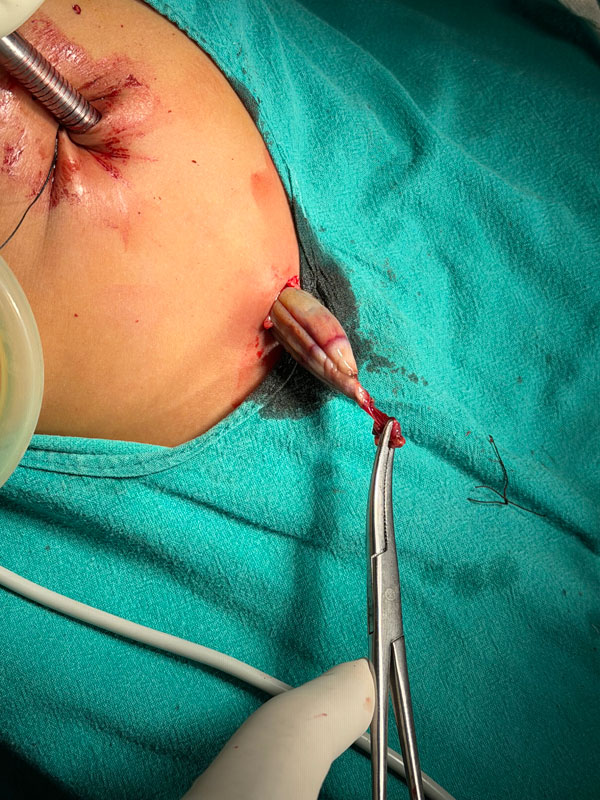

A Laparoscopic Ovarian Cystectomy was performed. Despite the torsion, we prioritized the preservation of ovarian tissue

Outcome: The baby was discharged the very next day.

Cosmetic Result: At follow-up, the abdominal scars are nearly invisible. The cosmetic and functional benefits of laparoscopy in infants—minimizing trauma to the abdominal wall—cannot be overemphasized.